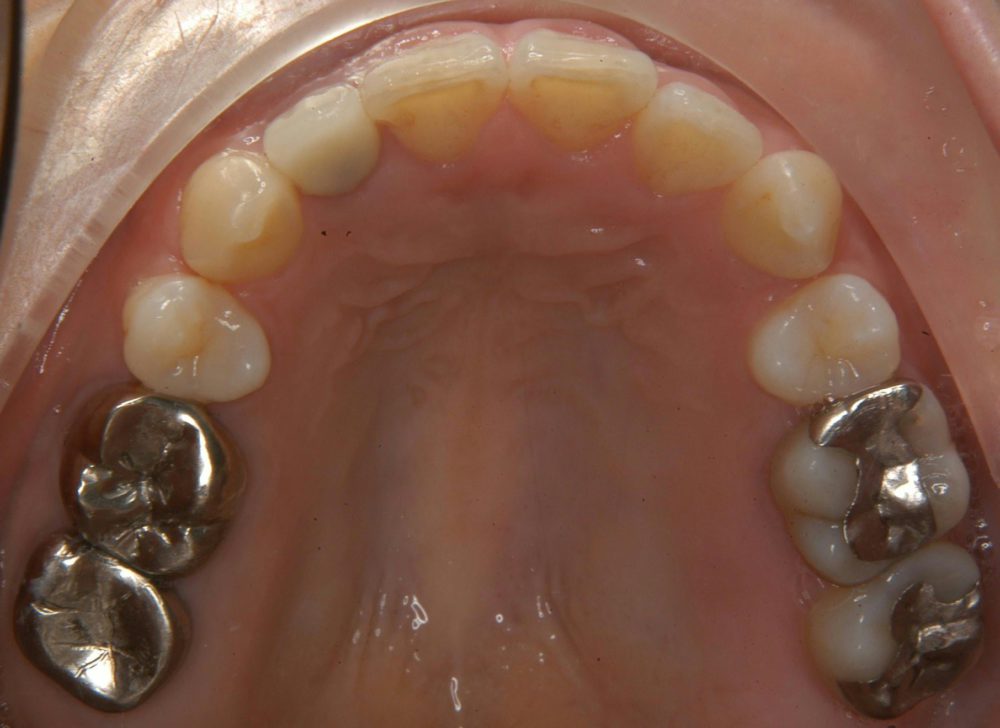

矯正と審美修復例

本症例は上顎右側側切歯が欠損している状態です。すなわち犬歯が側切歯の位置に配列しているので左右のバランスをとるために上顎右側第一小臼歯を抜歯して、犬歯を後方に移動し、側切歯のスペースを作りそこにインプラントを植立しました。

歯の裏側の矯正で、スペースを作ったり、犬歯を後方に移動させたりしたので、治療期間は3年を要しました。

主訴

不正咬合

診断名

叢生

年齢

34歳

装置名

舌側ブラケット

抜歯部位

上下顎左右側第一小臼歯

治療期間

3年

費用

総額約90万円(インプラント治療代含まず)

術前において歯や歯ぐきに疾病を招くリスクがあります

特別な副作用はありません

担当歯科医師

さっぽろ矯正歯科 院長

桜田 明宏

日本歯科専門医機構認定矯正歯科専門医